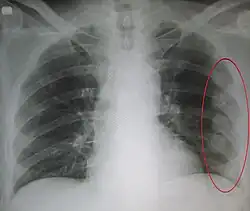

Plain X-rays often pick up displaced fractures but often miss undisplaced fractures.[13] CT scanning is generally able to pick up both types of fractures.[13]

Illustration showing rib fracture at 3rd, 4th and 5th rib -

Right sided pneumothorax and rib fractures -